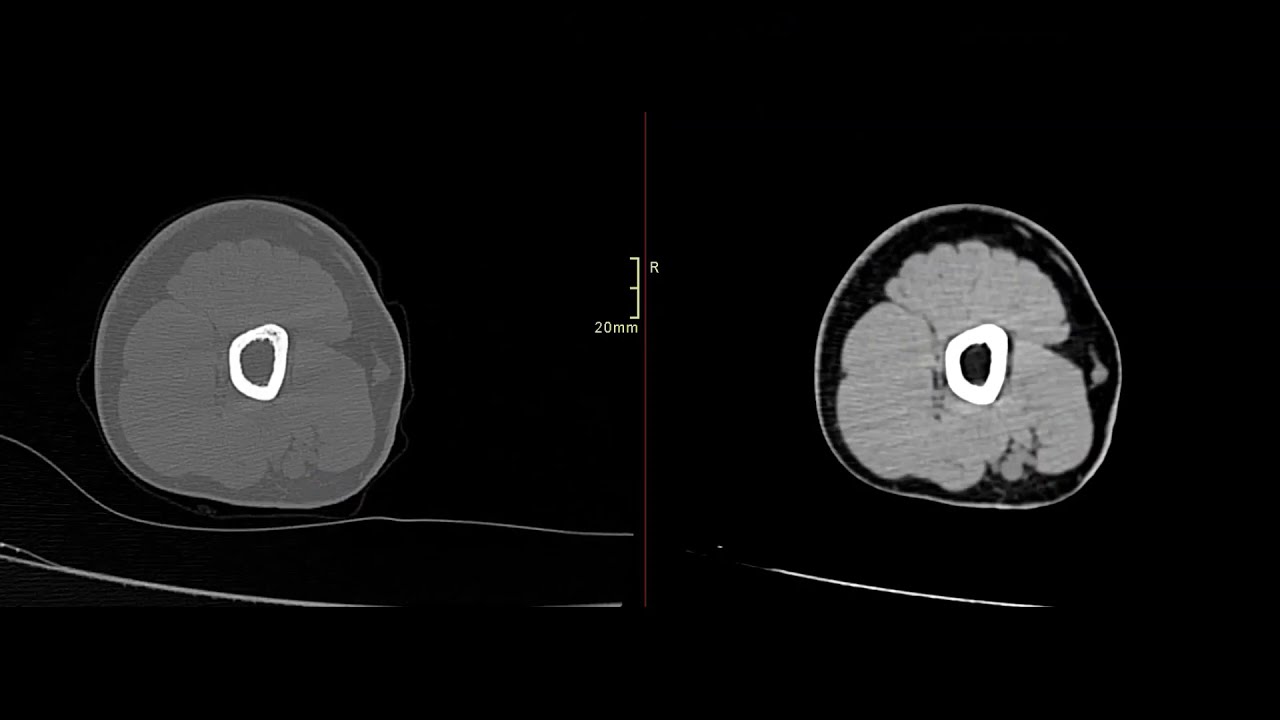

Для диагностики остеомиелита и оценки его распространенности назначается сканирование. Снимки пораженных участков помогают определить область некроза тканей при наличии абсцессов, которую необходимо удалить.

Компьютерная томография не используется для диагностики переломов локтя. Тем не менее, если боли после травмы сохраняются длительное время, сканирование может выявить очаги некроза и размягчения костей. Своевременное исследование костных структур помогает обнаружить начинающий остеоартрит.

Томография позволяет качественно оценить происхождение различных болей, возникающих при спортивных травмах. Двухмерные снимки с послойным изображением мягких тканей и хрящей помогают точно определить место травмы и характер повреждения.

Томография — это эффективный метод исследования локтевого сустава. МРТ предоставляет четкое изображение суставных поверхностей и хрящей, а также позволяет детально рассмотреть связки, сухожилия, мягкие ткани, кровеносные сосуды и нервные окончания. На основе выявленных отклонений от нормы специалист может установить следующие диагнозы: